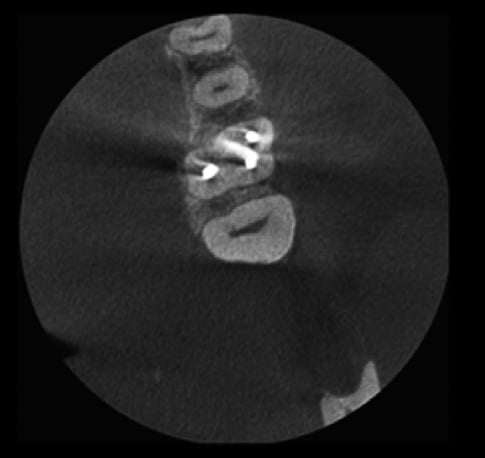

Bez usuwania artefaktów

Z użyciem algorytmu usuwania artefaktów Planmeca ARA

Metalowe uzupełnienia lub wypełnienia w zębach pacjenta mogą powodować cienie lub smugi na obrazie CBCT. Inteligentny system Planmeca ARA™ skutecznie usuwa te artefakty z obrazów Planmeca ProMax® 3D.